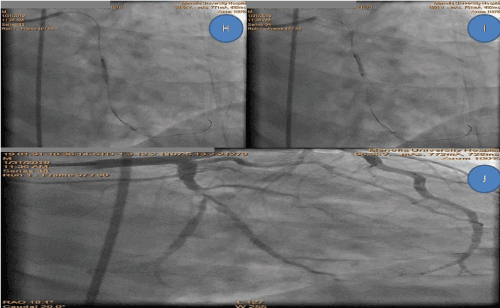

Figure 2. Final steps H, I, J of the technique with complete visualization of the vessel